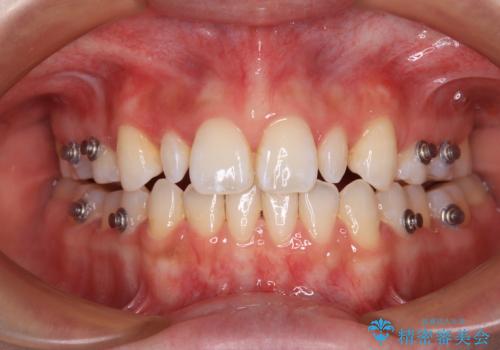

- 矯正装置

- インビザライン

遠方の地元へ転居する予定があるとのことで、インビザラインによる治療を希望されていらっしゃいました。

上下前歯同士の距離が離れているため、上顎左右第一小臼歯2本を抜歯することで前突を改善することとしました。